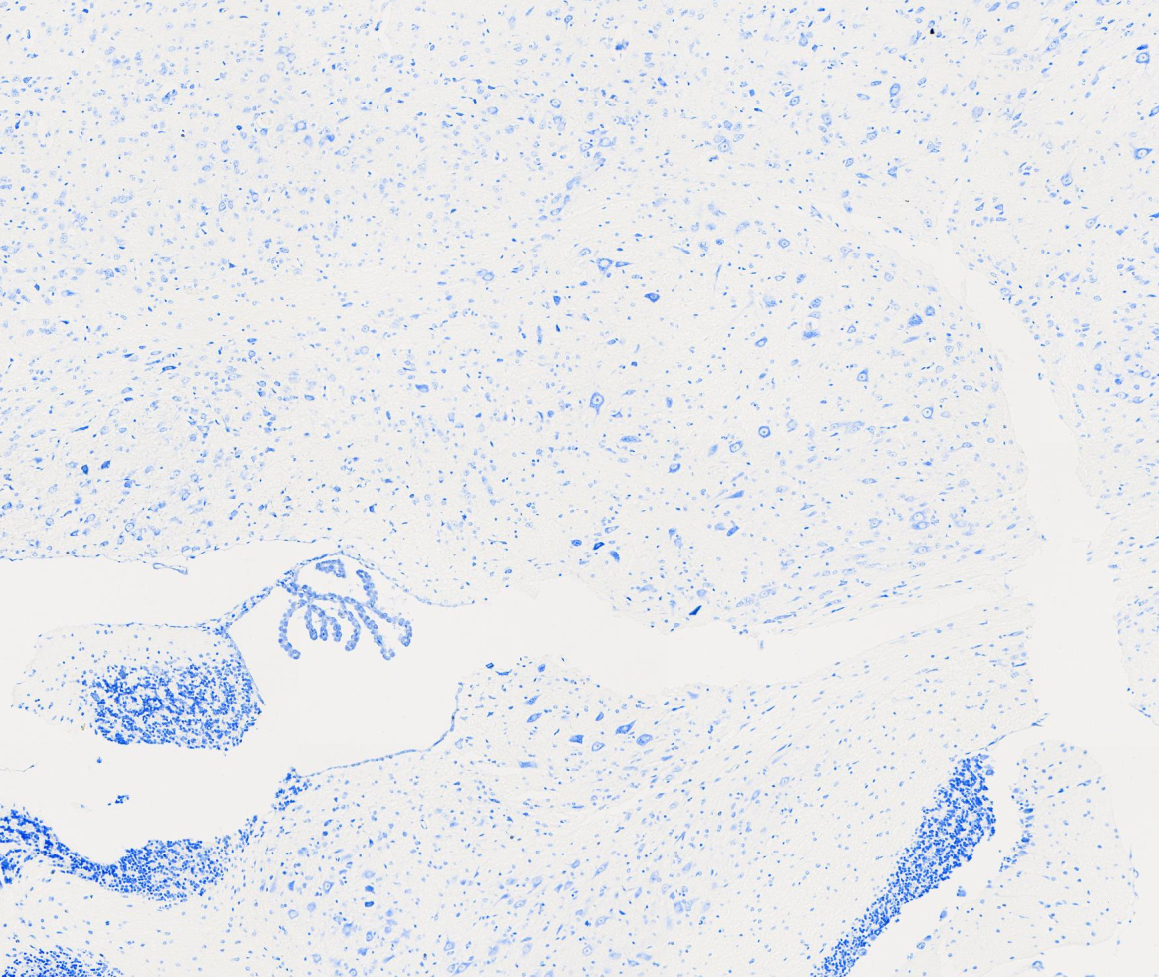

尼氏体染色

院校/单位:广州市粤斌医学研究有限公司

样本种属:小鼠

组织名称:脑

实验日期:2024-08-20